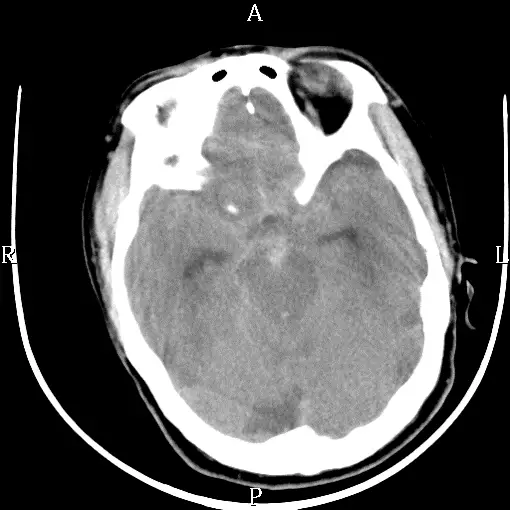

一位 70歲男性病人,有多年高血壓病史,沒有常規藥物控制。早上做晨間運動時,突然失去意識倒地不起,經119轉送急診,腦部電腦斷層掃瞄如下圖,最有可能的診斷為: 圖片描述

• 影像為非對比CT頭顱床層(axial view),可見多處高密度影分布在正常液體(CSF)應為低密度的部位。

• 在橋腦前池(prepontine cistern)及周圍基底池(basal cistern)可見明顯高密度帶狀影,代表血液積聚;同時Sylvian裂隙及大腦間裂隙內亦呈高密度。

• 腦室系統(側腦室、第三、第四腦室)內未見顯著高密度積聚且未見明顯擴大,排除大量腦室內出血或進展型阻塞性水腫。

• 未見局限性實質低密度區或水腫徵象,也無皮質下或硬膜下典型出血形態。整體高密度分布符合血液沿蛛網膜下腔(subarachnoid space)流布之表現。